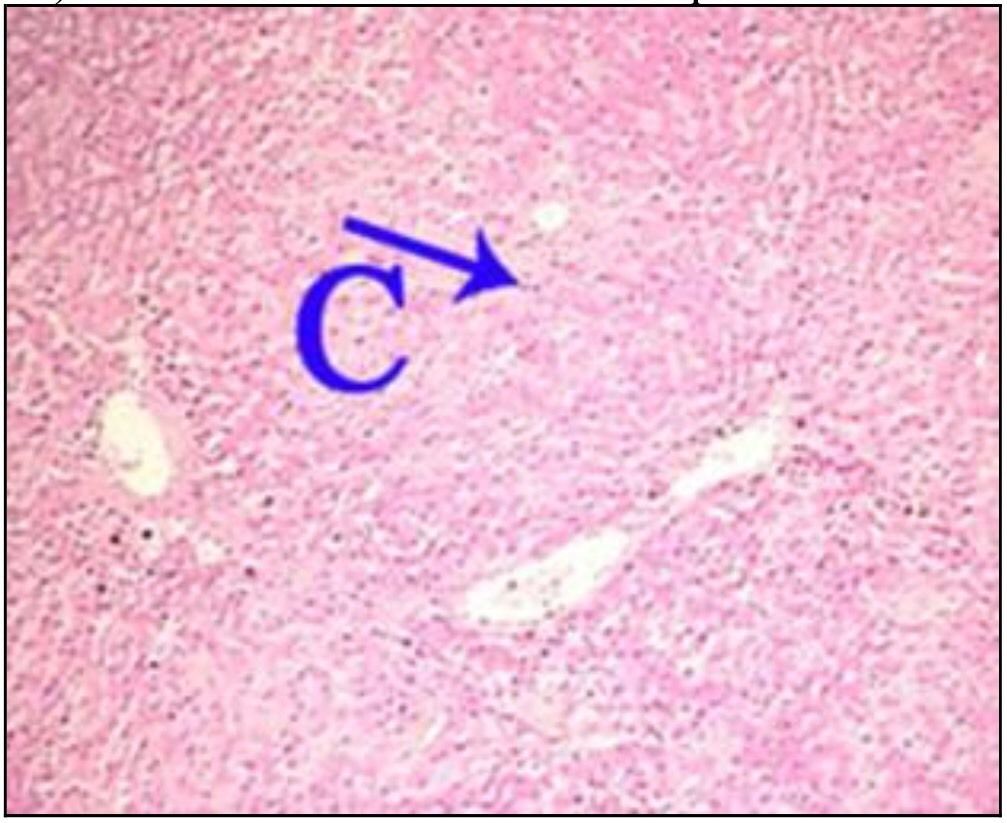

Question 13

Question

What is the correct answer at point C?

Answer

• - travées de sclérose annulaire

• - nodule cirrhotique, sans veine Centro lobulaire

• - néoformation canalicule biliaire

• - infiltration lymphocytaire

• - hépatocyte contenant de la bile

Question 14